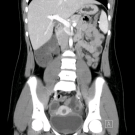

04/06/2023

An 11-year-old girl was brought to our emergency department by her parents with pain in the left lower quadrant of her abdomen. The pain had started approximately 4 to 5 hours prior to presentation.